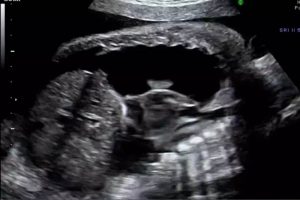

Diplomados en Ultrasonografía

Hola, conoce nuestros diplomados.